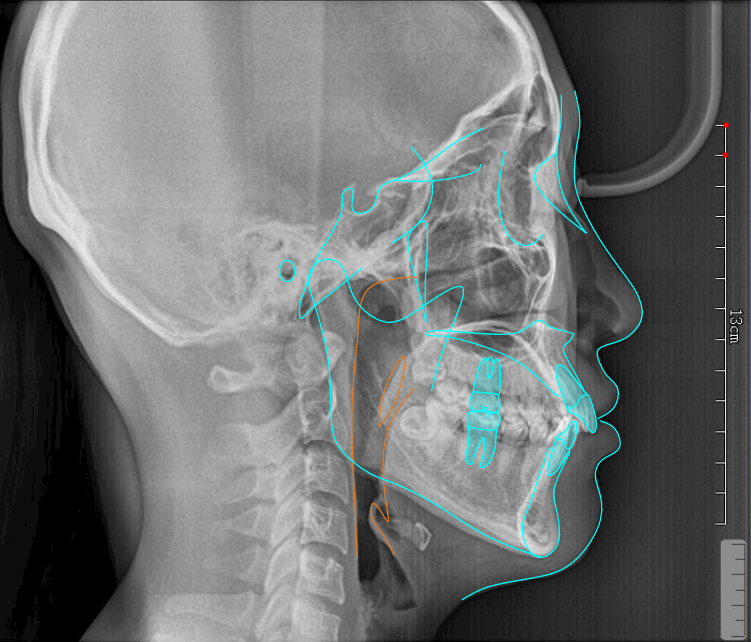

上下颌后牙远中直立(如图1-8所示)(远中直立相比较磨牙整体远移更加节省支抗)。为了保护前牙支抗、增加患者佩戴矫治器信⼼,选择少量多轮移动先排齐前牙再内收原则,尽量减少双推(同⼀象限内两颗牙同时远移),矫治中观察前牙支抗、为了抵消推磨牙向后产⽣的反作用⼒前牙要设计强支抗(上下四个象限颌骨钉植⼊或者使用间接支抗的⽅式)。

⽮状向:前牙先以12为基准排齐再内收2 ㎜,通过磨牙远移+前牙3~3不超0.3㎜ IPR获得间隙,前牙内收过程当中参考11保持转矩内收。下前牙内收过程当中保持转矩内收(参考41)、前牙正常覆盖结束。移动序列使用改良V-PATTERN’序列(如图1-9所示)每轮2㎜,前磨牙分开移动,5移动到位之后再移动4,均分⽮状向远移量, 后牙在远移过程当中增加冠远中轴倾角度,以根尖点为旋转中⼼(如图1-10所示)

上下颌初始与终末位置重叠。上颌以21为基准内收6㎜(如图1-11所示),下颌以31为基准内收3㎜(如图1-12所示)。内收过程当中要时刻关注前牙支抗(是否出现前牙唇倾)要根据前牙支抗情况,选择不同⼒值的皮筋牵引,需要注意的是,合理的移动序列比支抗钉更加重要。关注前牙支抗的同时也要关注后牙段,防⽌已经推到位的磨牙出现近中移动,有效的⽅法是在已经到位的磨牙制作TPA或使用间接支抗(如图1-12所示)。垂直向:该患者为均角,设计为通过伸长前磨牙压低后牙与下前牙整平下颌SPEE曲线,前牙正常覆合结束。SPEE曲线整平⽅式:对于⾼角患者、后部HE平面较陡的SPEE曲线主要通过压低后牙的⽅式整平。均角患者设计压低后牙与下前牙,伸长前磨牙的⽅式整平,低角患者希望更多通过升⾼后牙的⽅式整平SPEE曲线。⽔平向:以16、26为基准,不设计扩弓调整上下颌牙弓宽度。第⼀:参考Wala嵴(如图1-14所示),看颊侧是否有⾜够的骨量,通过测量FA点与 Wala Radge 的距离或参考CBCT进⾏判断)、磨牙的转矩(如图1-14所示),可以在电⼦扫描模型中的后视图当中进⾏观察(如图1-15)。后牙舌倾是扩弓的有利条件。如果磨牙已经是颊倾的状态,则不建议再设计扩弓,可在处⽅表当中向技师表明“以 16、26横向宽度为基准,维持现在的磨牙牙弓宽度”。